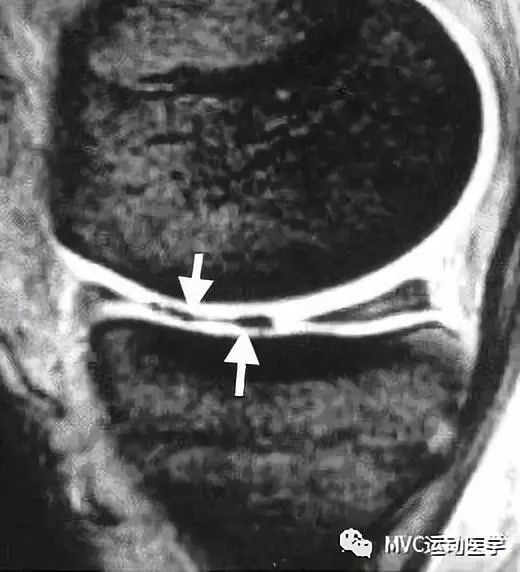

黑色箭头所指为半月板前角,白色箭头所指为撕裂的半月板向前移位